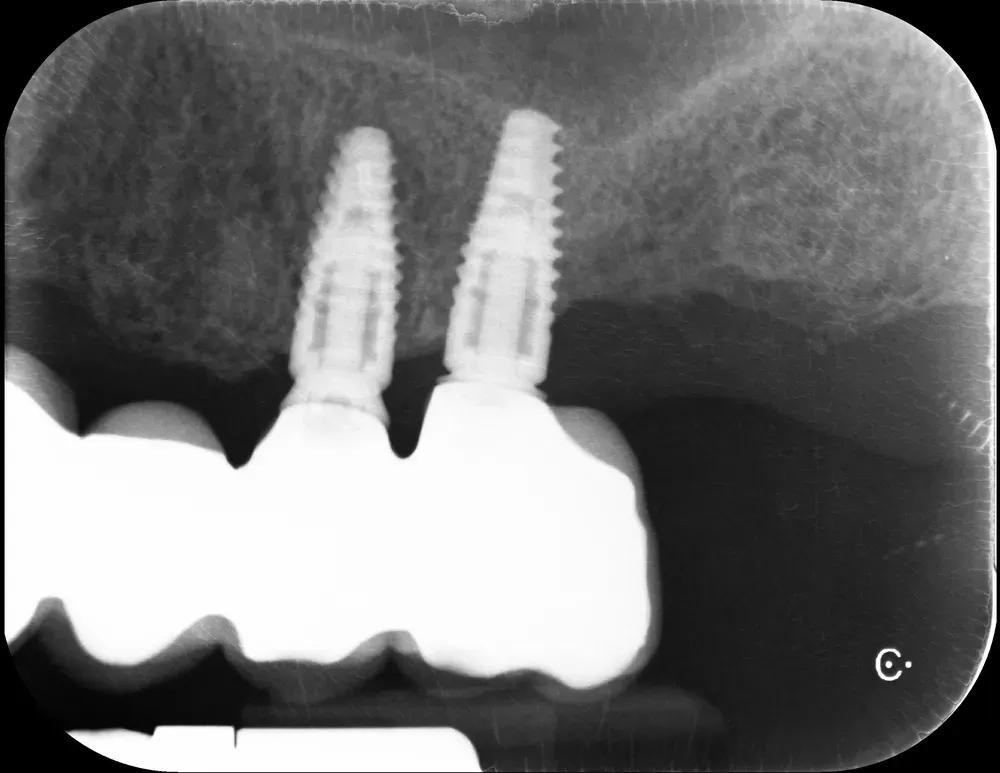

Il controllo a distanza di anni

Al controllo radiografico, sette anni più tardi, gli impianti sono in ottima salute e perfettamente integrati (vedi immagini seguenti).

Francesco viene regolarmente ai controlli, in particolare per le sedute di igiene professionale.